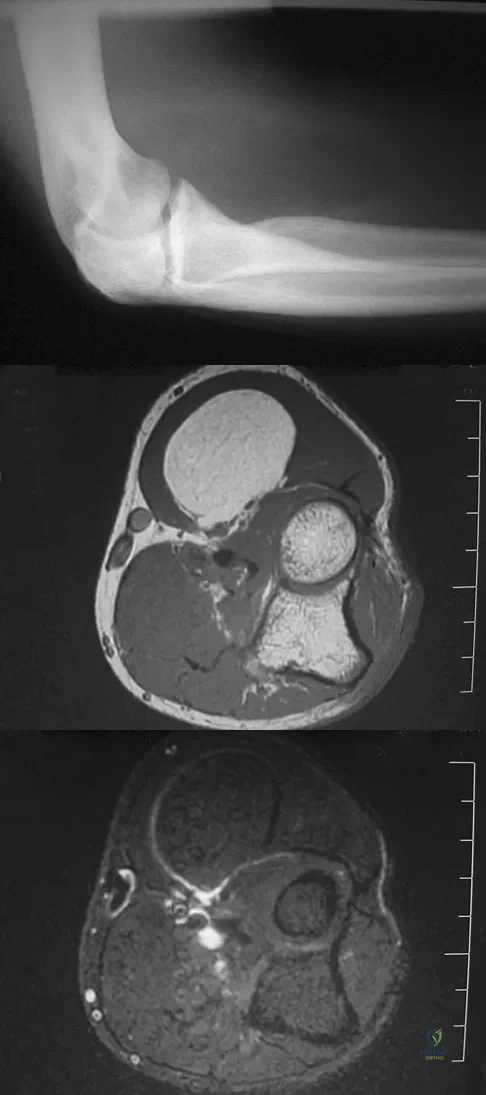

A 7-year-old girl has had a painful forearm for the past 2 months. Examination reveals fullness on the volar aspect of the forearm. Radiographs and an MRI scan are shown in Figures 42a through 42c. Biopsy specimens are shown in Figures 42d and 42e. What is the most likely diagnosis?

A 16-year-old girl has had painless swelling in her posterior left arm for the past 4 months. A radiograph, MRI scans, and an incisional biopsy specimen are shown in Figures 43a through 43d. What is the cytogenetic translocation most commonly associated with this tumor?

A 33-year-old man reports an enlarging painful soft-tissue mass in his right forearm. A radiograph and MRI scans are shown in Figures 45a through 45c. Treatment should consist of

A 20-year-old woman has had wrist pain for the past 5 months. A radiograph, MRI scans, and biopsy specimen are shown in Figures 46a through 46d. The patient is then treated with intralesional surgery. The patient should be counseled that her risk of developing lung metastasis is approximately what percent?